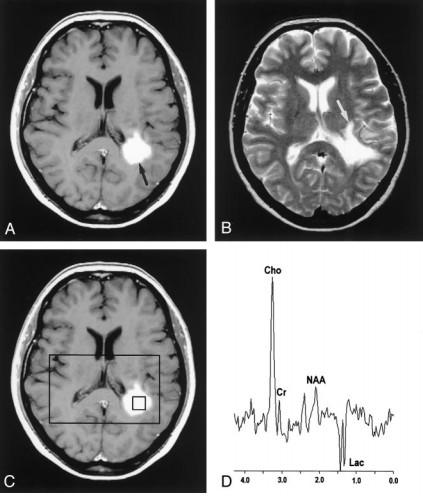

c/o H. Rowley, UW-Madison

c/o T. Kennedy, UW-Madison

Elevated choline indicative of membrane turnover

Loss of metabolites (“flat line” pattern) or lipid / lactate only c/o H. Rowley, UW-Madison